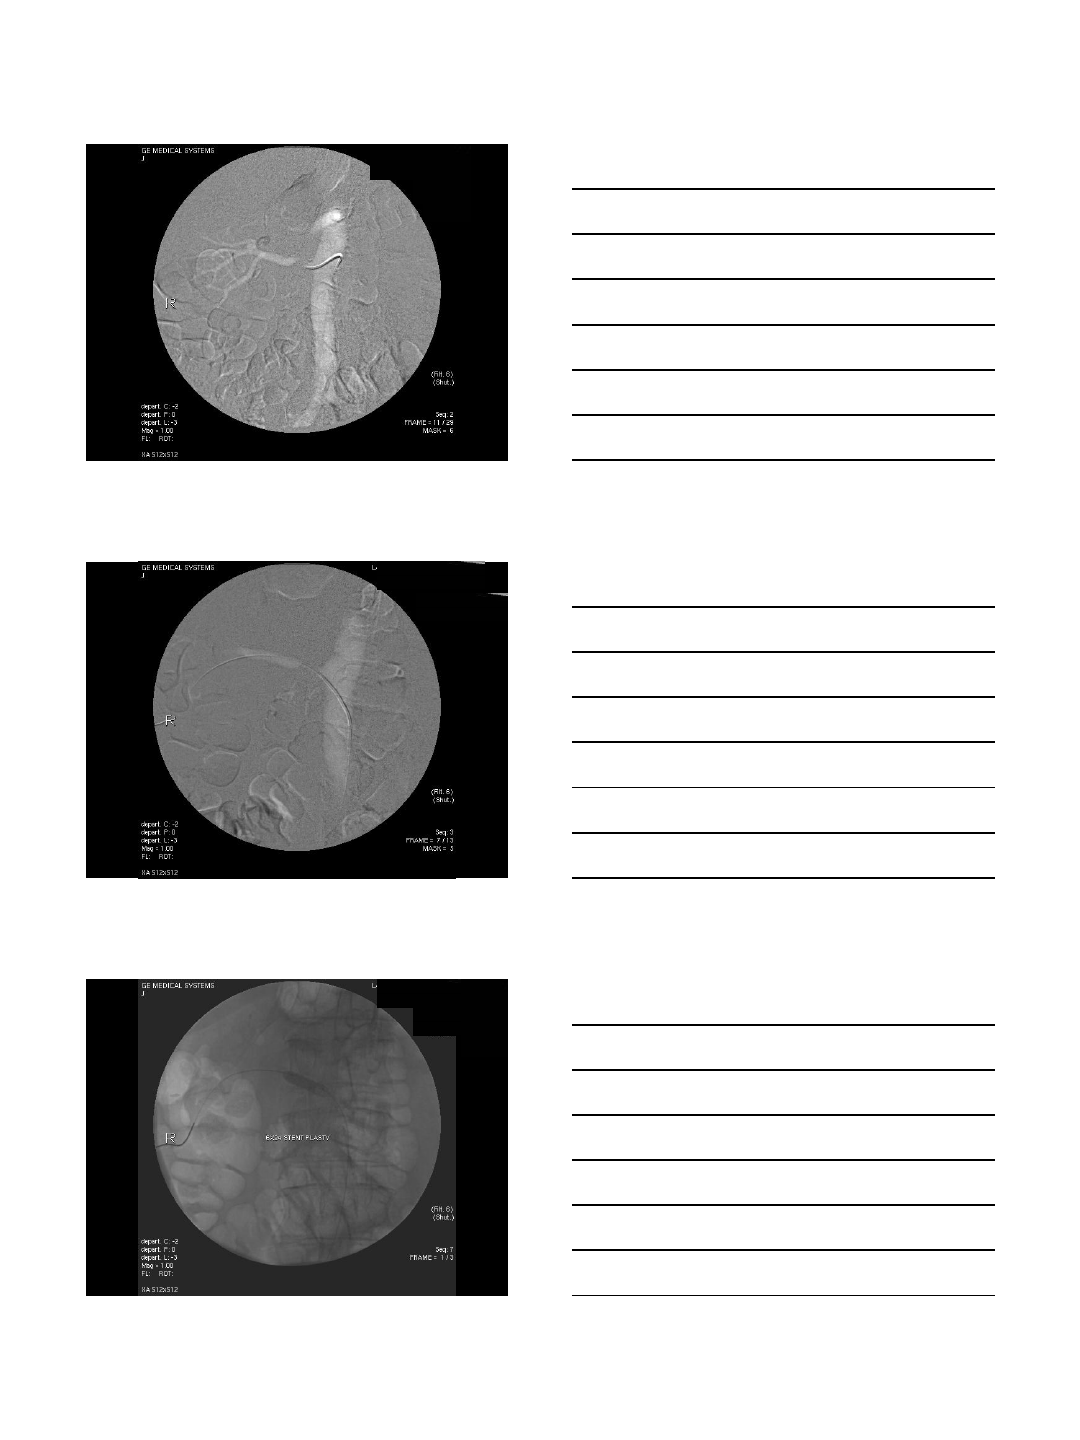

Carbon Dioxide Imaging

Subtracted Image Aorta filled with CO2 -

unsubtracted image

Carbon Dioxide Imaging with

Interventions